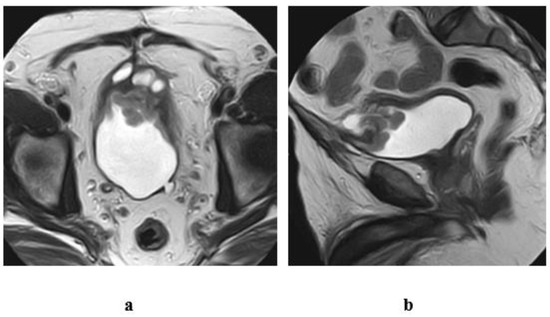

2.6.1. High-Resolution T2-Weighted Imaging (T2WI)

- Stage T1: Intact muscle layer adjacent to the tumor and displays hypointense SI at high resolution T2W sequence without early enhancement on dynamic study.

- Stage T2: Interrupted hypointense line of the muscle layer with early enhancement of the tumor with no extravesical fat invasion.

- Stage T3: irregular outer boundary of the tumor with distortion of the extravesical fat with the same SI of the tumor.

- Stage T4: Tumor infiltrates the surrounding organs or pelvic walls.

2.6.5. Inch Worm Sign